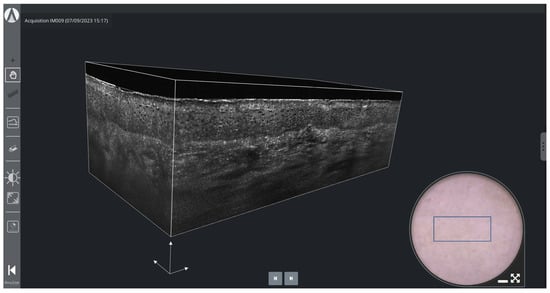

Figure 5 shows a 3D LC-OCT image of healthy skin (forearm of a 25-year-old woman). The volume-rendering visualization makes it possible to observe the three-dimensional architecture and connections of the structures in the skin at cellular level, which is not accessible by conventional histology. On the surface image, a blue rectangle indicates where the 3D image is acquired, allowing for easy positioning by the user.

Figure 5.

3D LC-OCT rendering and dermoscopy of healthy skin using deepLive™ software. The blue rectangle superimposed on the dermoscopic image delineates the location of the stack of horizontal sectional LC-OCT images. White scale arrows: 100 µm.